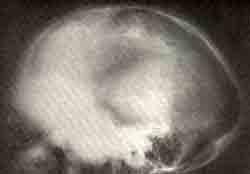

Деформация черепа при фиброзной остеодисплазии

Удлинение и сплющивание черепа, утолщение лобных костей в

результате разрастания диспластической ткани.

Наблюдалась в течение 6 лет: очень выросла (рост 183 см), правая нога укорочена на 5 см, имеет форму пастушьей палки. На правую ногу девушка не наступала из-за деформации, укорочения и болей при нагрузке. Значительно изменился и стал сплющенным череп.

Больная жаловалась на частое исчезновение зрения на 20 — 40 секунд. Изменений в глазном дне не выявлено. Исчезновение зрения было связано с колебаниями внутричерепного давления из-за резкой деформации черепа, его удлинения в переднезаднем направлении и выпуклости лобной кости. Консультант профессор-эндокринолог отметил лишь диффузное увеличение щитовидной железы.